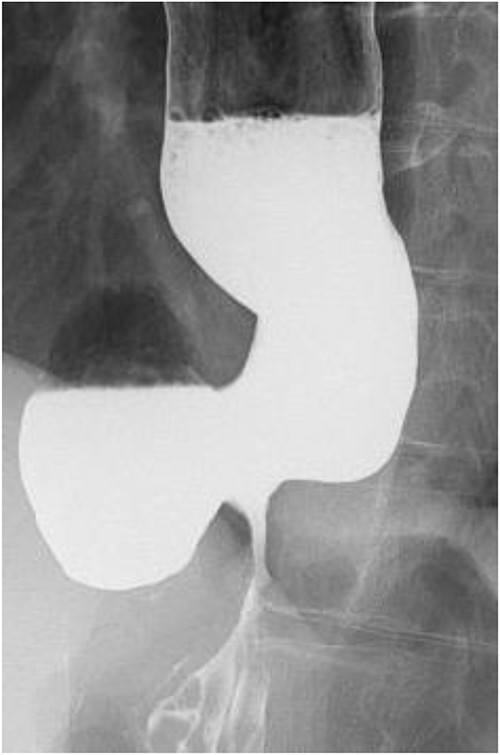

A 60-year-old female with dysphagia and vomiting visited the university hospital. In 2007, she underwent esophageal diverticulum resection (procedure unknown) with a diagnosis of an esophageal diverticulum, which subsequently recurred. In 2011, she underwent a transesophageal hiatus diverticulectomy and a fundoplication (Nissen procedure) at a local hospital. In 2013, dysphagia and vomiting appeared. The patient was diagnosed with recurrence and underwent balloon dilatation for follow-up. In 2015, the patient came to our hospital due to persistent symptoms. After one balloon dilation, the patient did not show any improvement and was referred for surgery. Esophageal fluoroscopy revealed a diverticulum 5 cm in size in the lower esophagus just above the eruption. There was no significant change in the diverticulum size before and after dilation (Figs 1 and 2). Gastrointestinal endoscopy revealed a diverticulum in the lower esophagus, with a residue accumulation (Fig. 3). The esophagus directly below the diverticulum was narrowed. The patient was diagnosed with recurrent lower esophageal diverticulum and underwent surgery.

Preoperative esophageal fluoroscopy (after dilation). There was no significant change compared to the pre-expansion period.